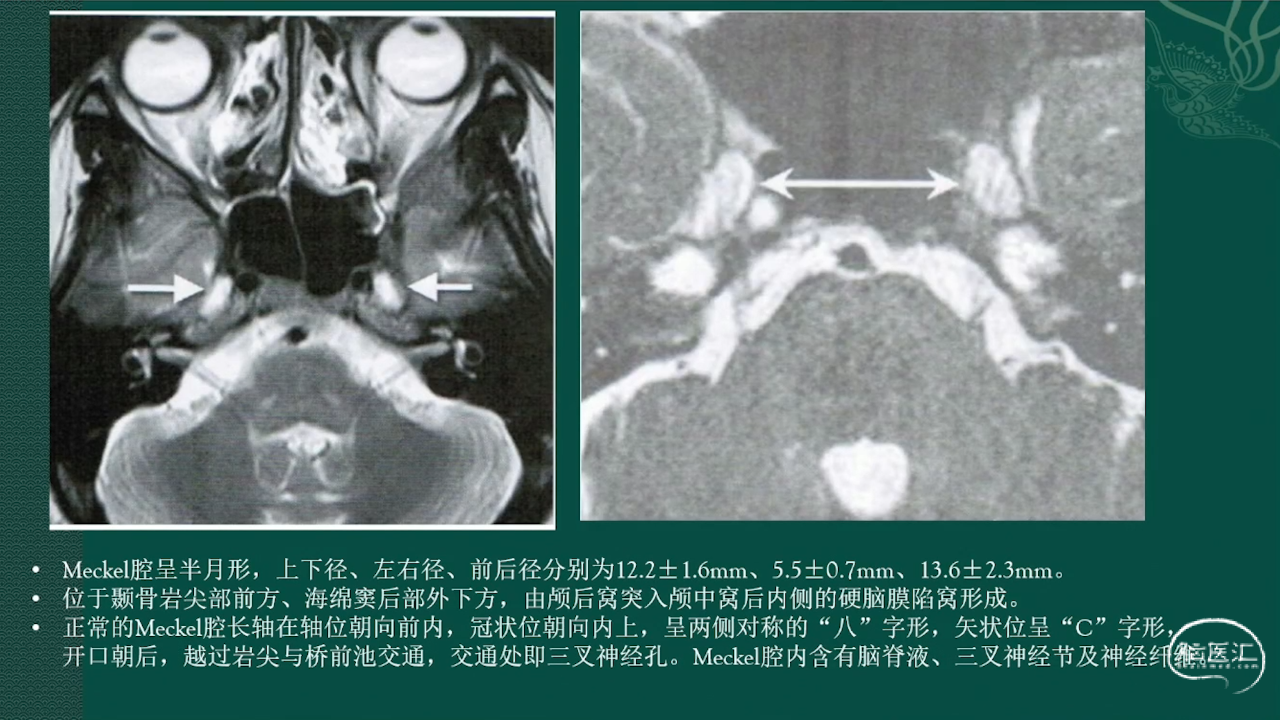

Meckel腔呈半月形,上下径、左右径、前后径分别为12.2士1.6mm、5.5士0.7mm、13.6士2.3mm。位于颞骨岩尖部前方、海绵窦后部外下方,由颅后窝突入颅中窝后内侧的硬脑膜陷窝形成。正常的Meckel腔长轴在轴位朝向前内,冠状位朝向内上,呈两侧对称的“八”字形,矢状位呈“C”字形,开口朝后,越过岩尖与桥前池交通,交通处即三叉神经孔。Meckel腔内含有脑脊液、三叉神经节及神经纤维。